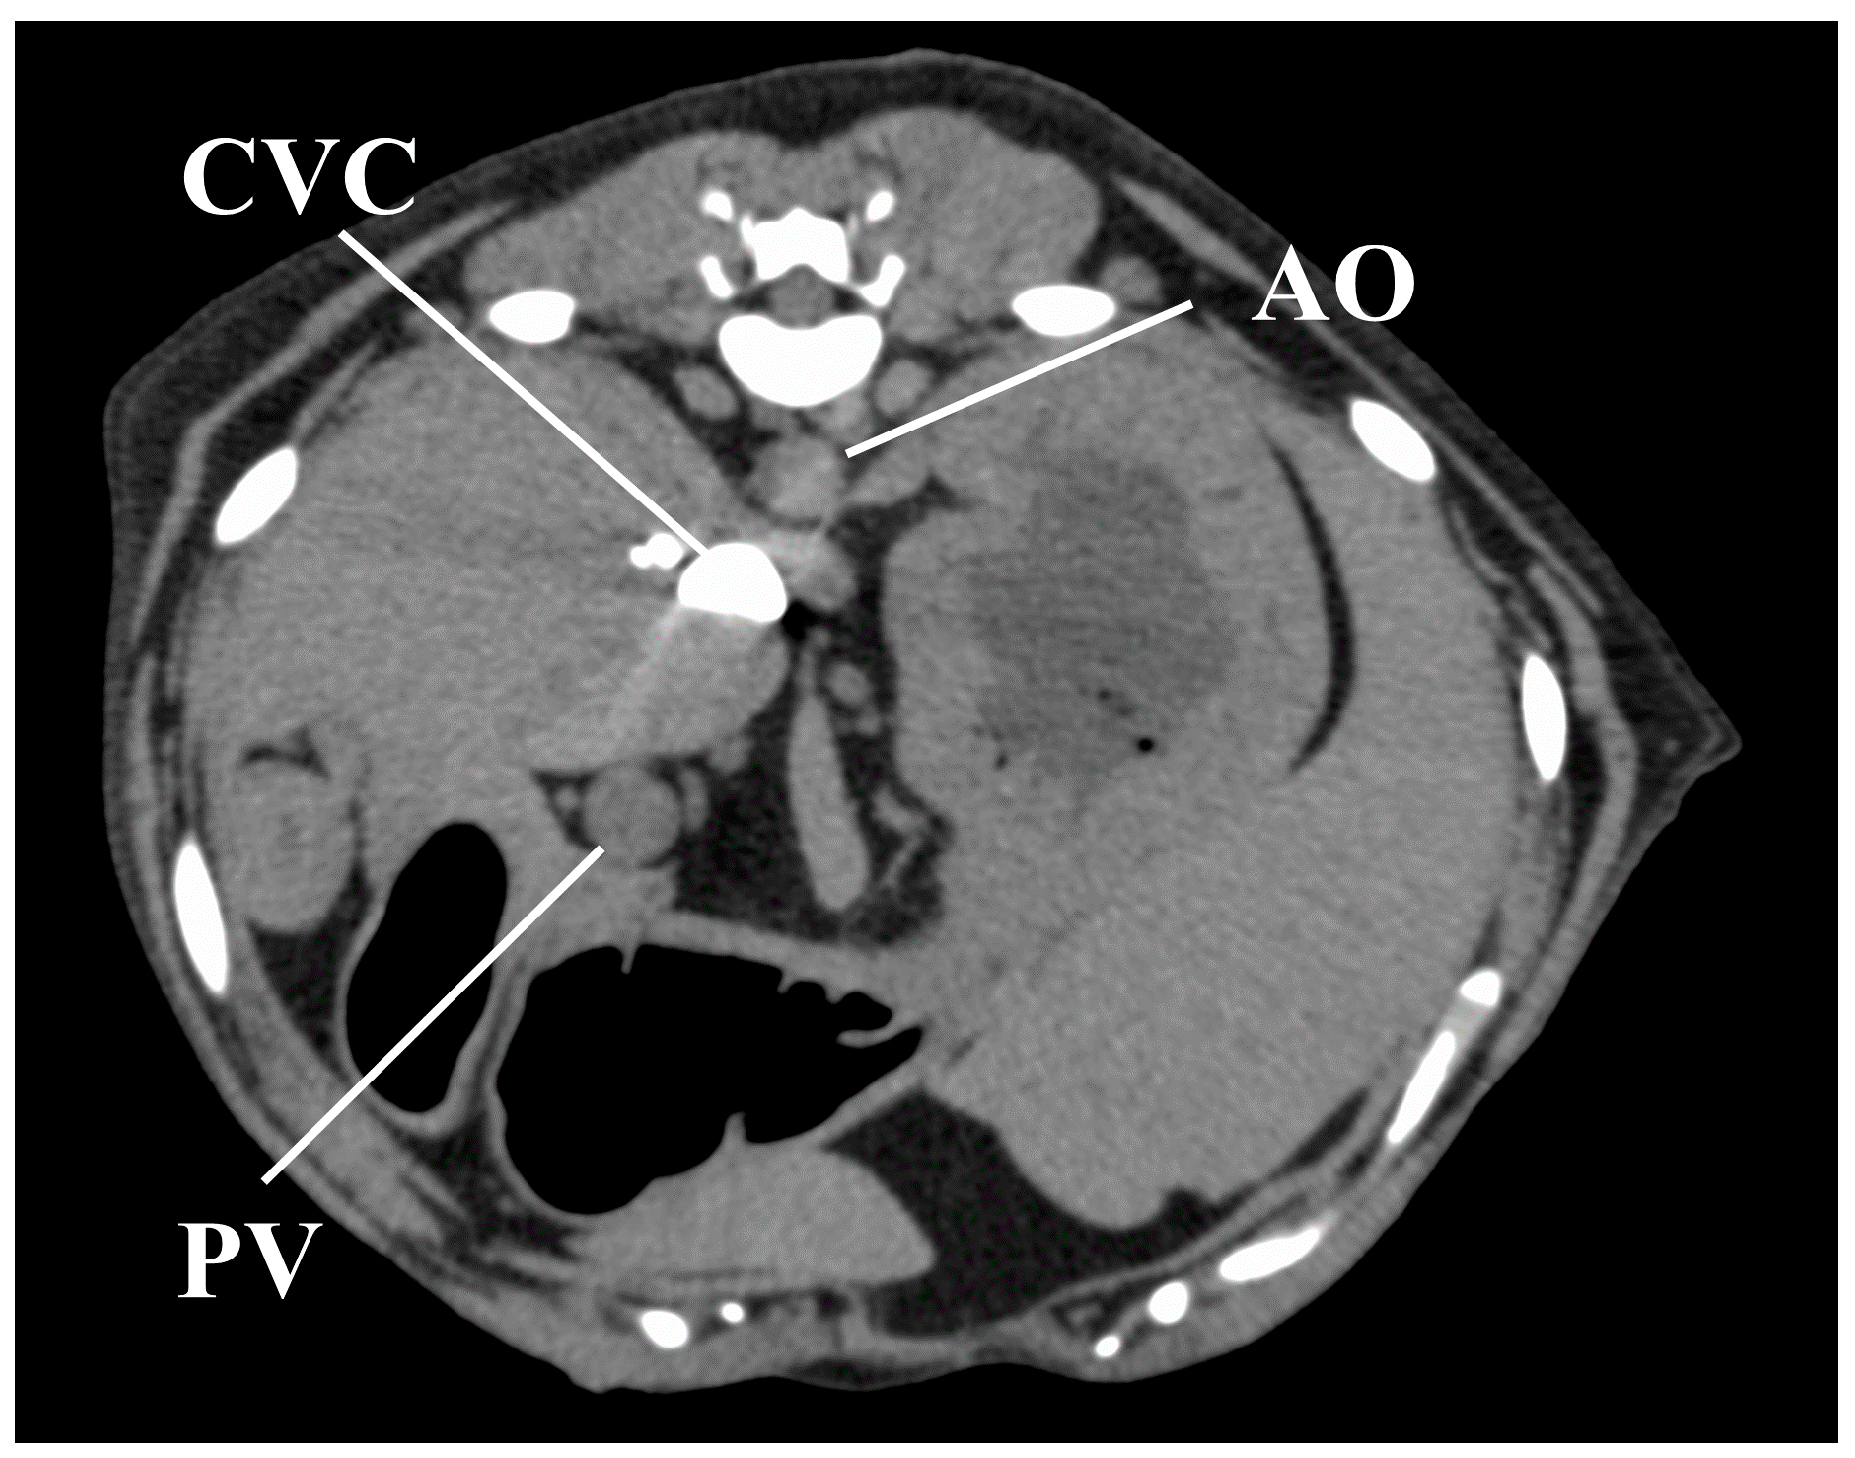

All CT images were reviewed on a dedicated DICOM viewer (OsiriX MD, Pixmeo SARL., Bernex, Switzerland). Contrast enhancement measures were obtained at the following regions of interest (ROIs; Figure 1): 40 mm2 area at the center of the AO, PV, and CVC, and a 200 mm2 area in either the left of right lateral lobe of the liver for HP measures, avoiding the hepatic vessels. All measures in the regions of interest (ROIs) were recorded in Hounsfield units (HU). The following time-based parameters were also measured from the time of contrast medium injection: first appearance of AO enhancement (AO-EA) and the AO enhancement peak (AO-EP); first appearance of CVC enhancement (CVC-EA) and the CVC enhancement peak (CVC-EP); first appearance of PV enhancement (PV-EA) and the PV enhancement peak (PV-EP); and first appearance of HP enhancement (HP-EA) and HP enhancement peak (HP-EP). The time-attenuation curve (TAC) was calculated based on all measured values in the ROIs.

Figure 1. Measurement of the contrast values for the hepatic vessels and hepatic parenchyma on a representative image obtained 50 s after injection for the anesthesia protocol. The contrast values of the aorta (AO), caudal vena cava (CVC), portal vein (PV), and hepatic parenchyma (HP) were measured by placing the region of interest (ROI) in the center of the AO, center of the CVC, the center of the PV, and right lateral lobar parenchyma, respectively. ROIs demarcated by red lines have an area of 40 mm2 and those in blue have an area of 200 mm2.